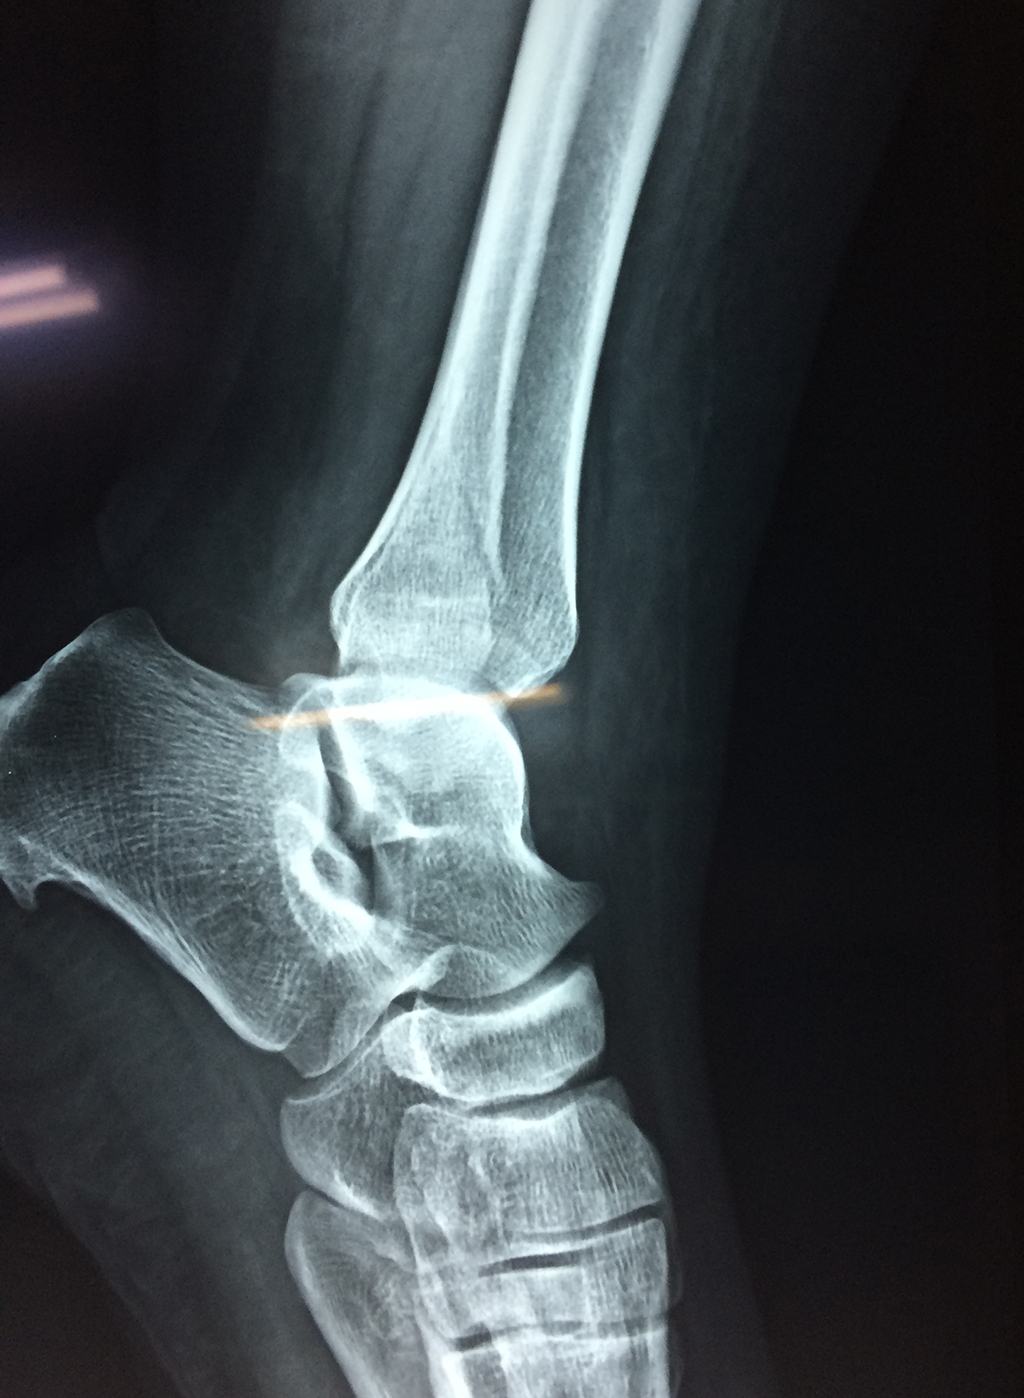

Cuando se necesita cirugía, es probable que esta implique el uso de clavijas de metal, tornillos o placas para sostener los huesos en su lugar mientras la fractura se consolida. Los elementos de soporte pueden ser temporales o permanentes.